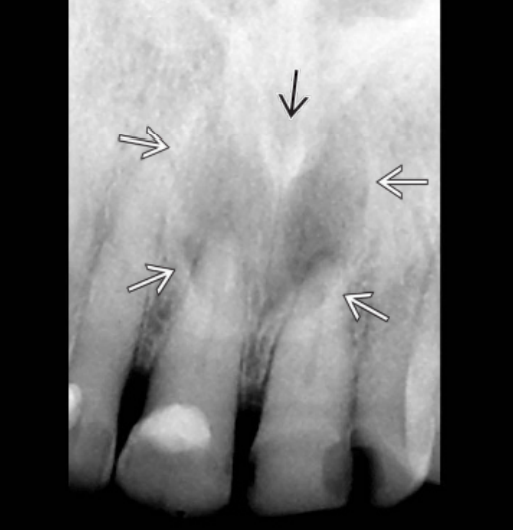

Οι περιακρορριζικές κύστεις είναι συνήθως ασυμπτωματικές και αποκαλύπτονται τυχαία κατά τη λήψη περιακρορριζικών ακτινογραφιών νεκρών οδόντων. Μια περιακρορριζική κύστη δεν μπορεί εύκολα να διακριθεί ακτινογραφικά από ένα περιακρορριζικό κοκκίωμα.

Σε κύστεις που υπάρχουν για αρκετό χρονικό διάστημα μπορεί να παρατηρηθεί απορρόφηση της ρίζας του υπεύθυνου δοντιού ή γειτονικών δοντιών. Οι περιακρορριζικές κύστεις θεωρούνται μια από τις συχνότερες, αν όχι η συχνότερη, αιτία εμφάνισης διόγκωσης στις γνάθους. Συχνά οι ασθενείς δίνουν ιστορικό παρουσίας χρόνιας, βραδέως αυξανόμενης διόγκωσης, η οποία αρχικά είναι σκληρής συστάσεως ανάλογης οστού. Καθώς η κύστη αυξάνεται, και παρά την εναπόθεση νέου οστίτη ιστού, το οστικό τοίχωμα της κύστης λεπταίνει βαθμιαία και η διόγκωση δίνει την εντύπωση κελύφους αυγού. Μόνο όταν ραγεί το οστικό τοίχωμα της κύστης μπορεί να παρατηρηθεί κλυδασμός. Στην άνω γνάθο η διόγκωση μπορεί να επεκτείνεται τόσο παρειακά όσο και υπερώια, ενώ κατά κανόνα στην κάτω γνάθο η διόγκωση επεκτείνεται παρειακά.

! Η ύπαρξη ενός νεκρού δοντιού είναι εξ’ ορισμού απαραίτητη για να τεθεί η διάγνωση της περιακρορριζικής κύστης.